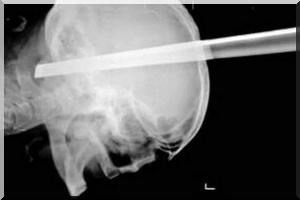

altUn Serbe a survécu miraculeusement après avoir eu le cerveau transpercé par une barre de fer au cours d'une bagarre dans un bar.

Seule certitude: il a échappé au pire. Car son cerveau avait été transpercé par une barre de fer de onze centimètres. "Nous avons retiré le corps métallique de la tête du patient sans complications", confie le neurochirurgien Pavel Rudenko